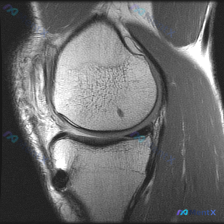

今天分享一例膝关节MRI读片的分析思路,问题是:图像里能发现什么异常,和提问提到的「软骨异常」有什么关系? 病例影像基础信息 这是一张膝关节T1加权矢状位MRI图像,对比度良好,显示膝关节前部结构:髌骨、股骨远端滑车、胫骨近端和髌下脂肪垫,左侧为前侧,右侧为后侧,上为头侧下为足侧。 系统性观察结果...